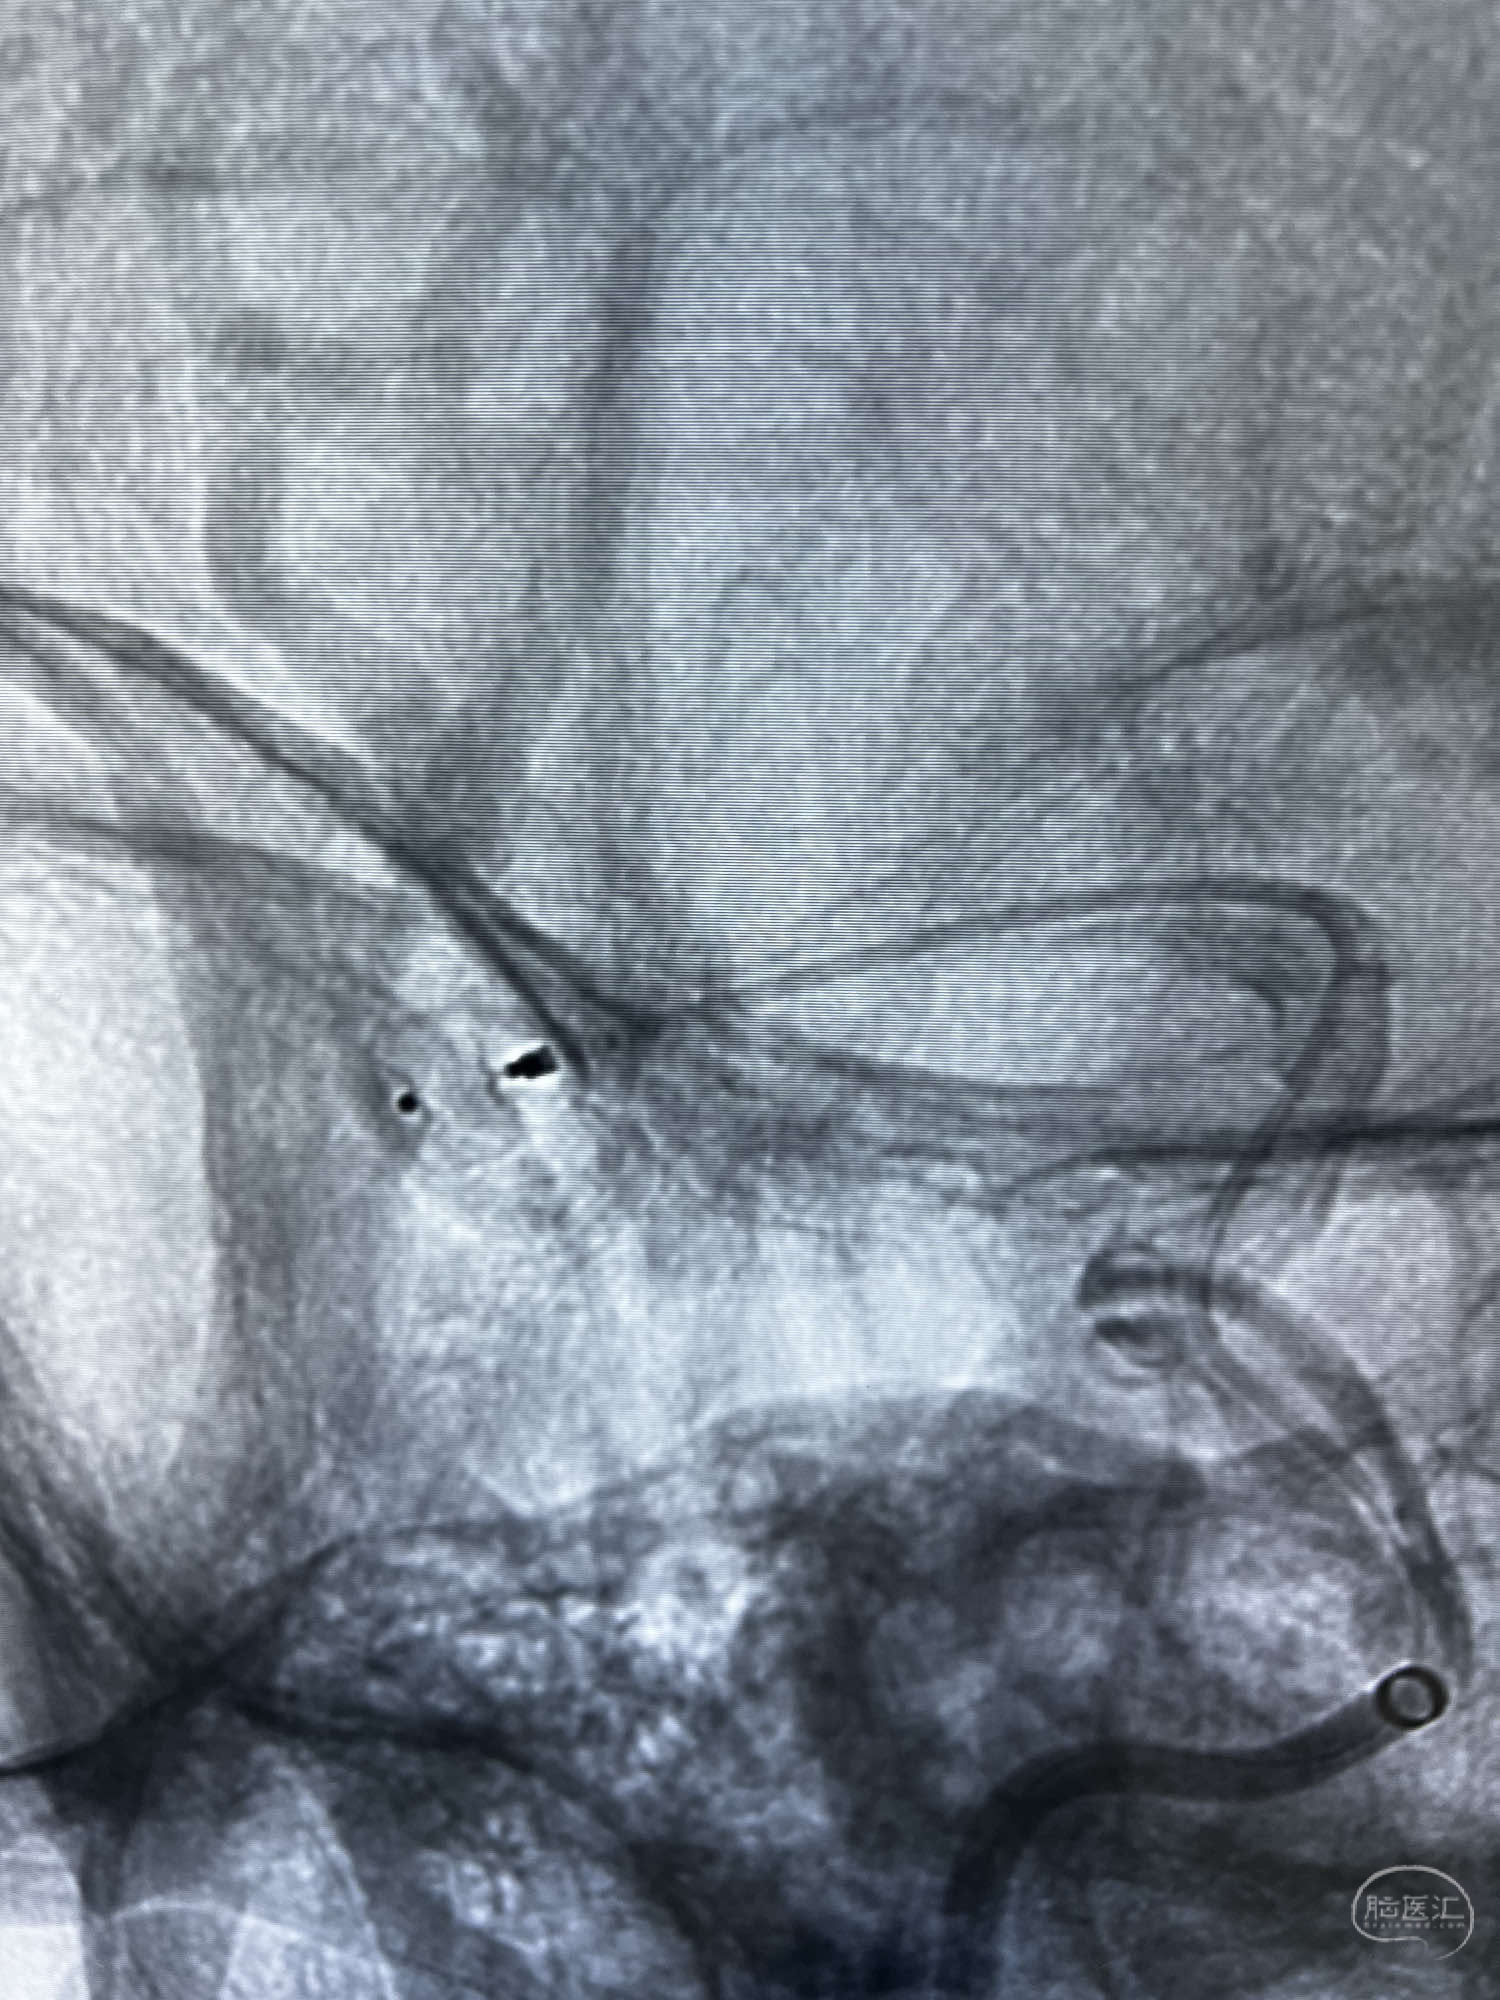

6F Neuromax➕6F115cm 心玮中间导管建立路径,sychro14微导丝➕VIA21超选至动脉瘤体内近中部,WEB5mmx3mm植入动脉瘤。

WEB瘤内扰流装置5mmx3mm经过“种子、萌芽、开花”三个阶段,打开后良好贴壁,动脉瘤内血液滞留,载瘤动脉通畅。WEB一步到位,通过瘤内扰流的方式起到栓塞动脉瘤的作用,避免了应用支架保护分支血管,简化了操作步骤,降低了术中血栓及出血的风险。